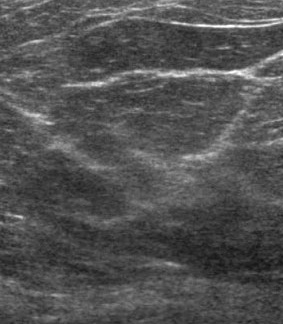

– Ultrasounds are far less painless than mams; a high-frequency sound wave test is used for those with dense breast tissue and/or to further review an unclear mammogram. The technician squirts a standard ultrasound gel on your breast before running a wand-like device over the area where the lump is located. results are made available within a few days, maybe sooner.